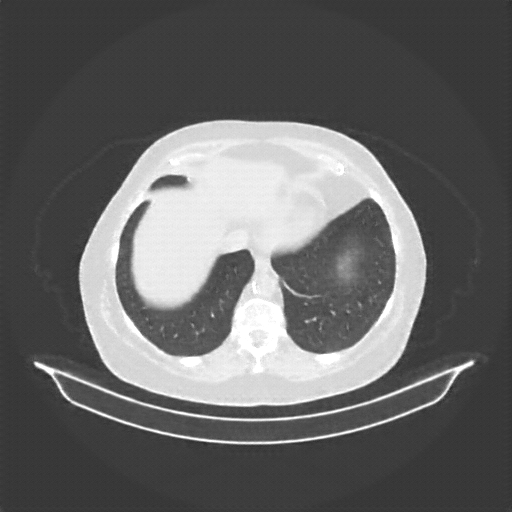

Generated VENOUS CT scan (A→B translation)

Lung window (WL -600, WW 1500 β†’ Low βˆ’1350, High +150)